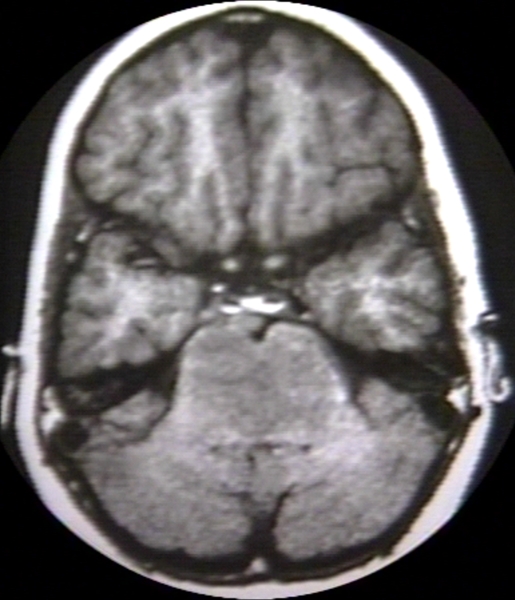

RADIOLOGY: NERVOUS: BRAIN: ASTROCYTOMA, CEREBELLOPONTINE ANGLE; - SFMRC - BASILAR ARTERY ENCASED - A (MRI)